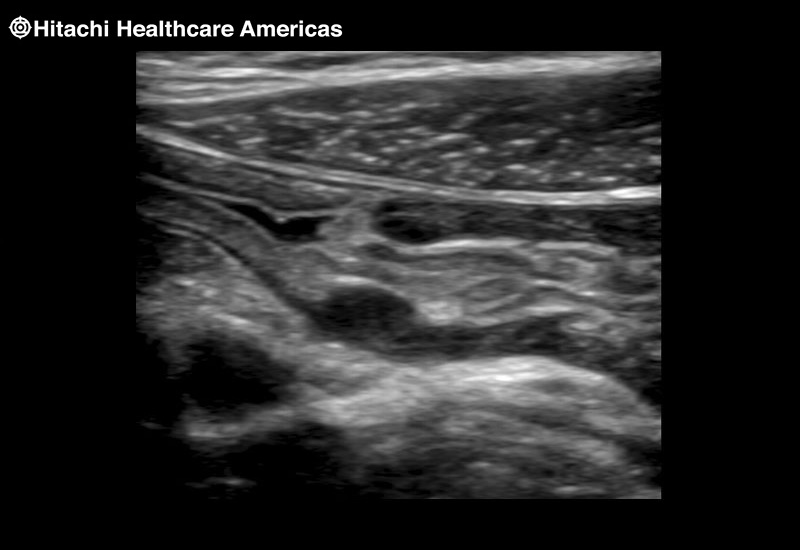

Superior guidance for all applications

Fujifilm Healthcare Americas is committed to designing tools that help surgeons navigate inside the human body and provide the necessary information to immediately make critical surgical decisions.

Fujifilm Healthcare's dedication to Surgeons provides outstanding ultrasound technology, professional support and the specialized tools necessary to best perform comprehensive real-time ultrasound imaging in Breast Surgery, General Surgery, Laparoscopic Surgery, Neurosurgery, Robotic Surgery and Surgical Oncology.